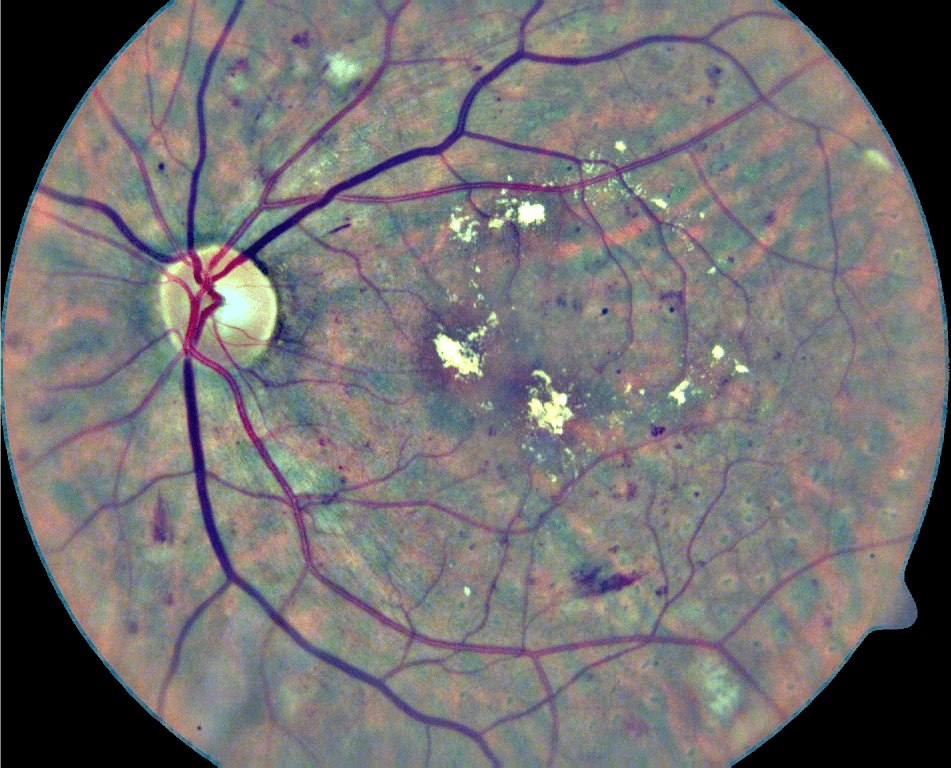

In its early stages, DR might be clinically asymptomatic (Abràmoff et al., 2010). As a consequence, this condition is typically identified when it is more advanced and treatments are significantly less effective (Mookiah et al., 2013). A recent study has shown that 44% of hospitalized patients with diabetes remain undiagnosed (Kovarik et al., 2016). To prevent this, people suffering from diabetes are usually recommended to be regularly examined through fundus images to verify the non-existence of red lesions (Abràmoff et al., 2010). Although fundus photographs are currently the most economical non-invasive imaging technique for this purpose, manual diagnosis requires an intensive effort to screen the images (Mookiah et al., 2013). Red lesions appear as small red dots that might be subtle and too small to be detected at first glance (Figure 1). Large HEs, on the contrary, are more evident and less difficult to visualize.

Finally, qualitative results for a randomly selected image in the DIARETDB1 test set are depicted in Figure 10. Green circles are detected lesions according to the ground truth labeling provided in the data set, while yellow circles correspond to lesions detected by our method but that are not labeled in the ground truth. Finally, red circles surround the lesions that were manually annotated as true lesions but were ignored by the method. Qualitatively, many of the yellow circles appear to be microaneurysms or hemorrhages that were not detected during manual labeling due to their subtle appearance in the original RGB image.